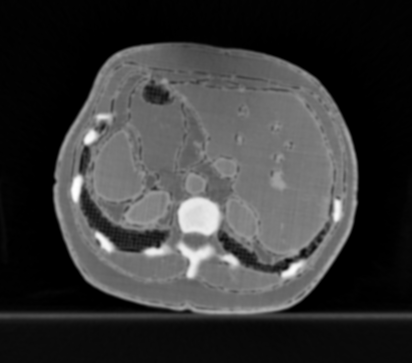

3.1.3 Example 2: data driven reconstruction methods in lung CT screening

There is sufficient evidence that screening for certain tumours using CT images may improve prognosis of cancer survivability (citep \@BBN(Boiselle, 2013)). As mentioned above, in order to gain better image quality with less X-ray dose, many enhanced regularization techniques with integrated machine learning steps have been suggested for CT reconstruction, and in a full reference setting they are commonly evaluated by applying PSNR and SSIM, see e.g. (citep \@BBN(Adler and Öktem, 2018; Hendriksen, Pelt, and Batenburg, 2020; Unal, Ertas, and Yildirim, 2021)). As CT images are generally taken to perform a clinical task, they are not the final step of a medical process but often the initial one. Therefore the definition of what makes a good image heavily depends on the task in hand, and for prognosis related cancer the identification of tumours is of upmost importance.

In on-going research on photon counting detector types and screening procedures for lung cancer (EPSCR grant: EP/W004445/1) an experiment was conducted testing enhanced reconstruction algorithms. Simulations using less than 10% of a clinical X-ray dose were performed to investigate if data-driven methods could sufficiently enhance the images to clearly see the tumours in the lungs while providing very low amount of dosage to the patients. The corresponding data was a CT-dose simulation, using images from the open LIDC-IDRI dataset (citep \@BBN(Armato et al., 2011)) as references, as well as simulated and reconstructed images with in-house software. Figure 3 shows the results of the experiment. We show the reference image used as basis for the simulation, together with five different reconstruction algorithms. The first is an iterative solver, a gradient descend algorithm with TV minimization (citep \@BBN(Sidky et al., 2012)) and (c)-(f) correspond to machine learning methods: FBPConvnet is a denoising algorithm that cleans the bad image (citep \@BBN(Jin et al., 2017)), LPD is an iterative unrolled method that combines traditional solvers with machine learning (citep \@BBN(Adler and Öktem, 2018)), Noise2Inverse is a self-supervised learning method (i.e. does not require ground truth data) (citep \@BBN(Hendriksen et al., 2020)) and ItNet is another iterative unrolled method, the best performing winner of the AAPM DL-Sparse-View CT challenge (citep \@BBN(Genzel, Macdonald, and März, 2021)). ItNet is also judged here as the best result according to PSNR, SSIM and LPIPS.

Refer to caption

(a) Reference

(b) (27.6, 0.70, 0.37)

(c) (31.9, 0.73, 0.29)

(d) (32.5, 0.84, 0.19)

(e) (32.5,0.77, 0.20)

(f) (33.0, 0.89, 0.12)

Figure 3: Reference image (a) and outputs of different reconstruction methods (b)-(f) applied to dose simulated data. PSNR/SSIM/LPIPS are unable to identify the best reconstruction (c), where also the tumour is visualized well.

FR-IQA mismatches

This experiment was performed to evaluate the quality of different kinds of CT reconstruction, and especially the lung tumour detection capabilities thereof. The best result according to the chosen IQA measures is given by ItNet in Figure 3(f), which performs visually poorly. Not only the tumour (zoomed in white circle) is significantly less visible in the reconstruction, but ItNet also produces structures in the lung that are different than the ones in the reference image; it blurs and lengthens much of the soft tissue present in the lungs and it also created structure from noise in some places. Moreover, the image is overly smooth. Comparing the other reconstruction algorithms, it seems that FBPConvnet Figure 3(c) is the one performing best at preserving the shape of the lung nodule, even when the resulting image contains enhanced pixel-level noise.

We can see here that the qualitative findings strongly contradict the numbers provided by the selected measures. The reconstruction of ItNet, Figure 3(f), is outperforming the other reconstructions in regards of the measures, and the qualitative winner FBPConvnet, Figure 3(c), is judged as second worst by the same measures. This experiment suggests that the discussed measures are not a good choice for that kind of CT reconstruction applications and are yielding misleading results.

While pixel-independent random noise may be a worse effect in a natural image than a slightly oversmooth reconstruction, this is not true in CT images, where small structures may disappear if smoothing is promoted against edge preservation. In iterative reconstruction algorithms such choices are explicitly made by choosing the prior appropriately, in data-driven models the researcher has limited control on the type of implicit priors the algorithm learns from the data, i.e. model builders do not know what the algorithms chooses to learn from the ground truth. In these cases appropriate evaluation would therefore be even more important to ensure quality. If this is followed by a blind evaluation using non-appropriate metrics, the promotion of less desirable images can happen, chosen by an implicit assumption on the metric rather than the actual goal of the task.